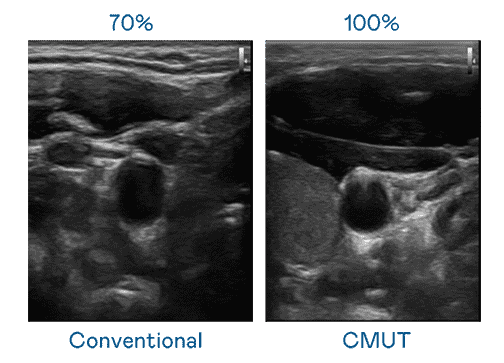

CMUT 技术是一种用电容式微机电元件来产生超音波讯号的技术。。。与传统 PZT 压电式技术相比,,CMUT 频宽增加 30%,,,,更宽频的超音波讯号让影像解析度大幅提升,,是实现高影像品质医疗超音波扫描、、、促进精准医疗发展的关键技术。。。。

大频宽带来超清晰影像

超音波影像的解析度高低,,,首先取决于探头能发出的讯号频宽。。。尊龙z6 CMUT 可提供高清晰的超音波讯号,,,,提供高频宽、、、、高灵敏度、、、、影像纹理细节更高的超音波影像,,,,协助医护人员缩短影像判读时间及利用精准的医疗影像进行诊断。。